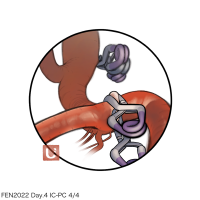

FEN2022シリーズ